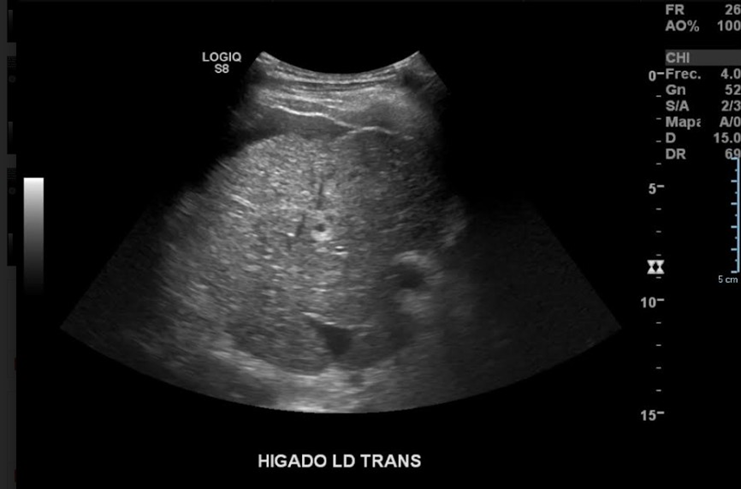

Hígado de parénquima heterogéneo, aumento de tamaño del lóbulo caudado, contornos lobulados, vena porta de calibre y flujo conservado (hepatópeto). Presencia de líquido subfrénico der, izq e interasas. Acompañado de esplenomegalia. Sugerente de daño hepático crónico. En región supra diafragmática derecha, se observa moderada cantidad de líquido anecogénico, de contenido homogéneo, sugerente de derrame pleural.

Hallazgos: Hígado de forma, tamaño y ecogenicidad normal. Sus bordes se observan ondulados y sus ángulos romos. No se observan lesiones focales. Presencia de líquido perihepático.

Bazo de ecoestructura normal, con tamaño aumentado; mide: 19.0 cm.

Impresión: Imágenes evidentes de daño hepático de larga data; complementar con estudios funcionales.

Esplenomegalia.

Ascitis.

Se observa ocupación de seno costofrénico derecho; por elemento líquido, en correspondencia a derrame pleural.